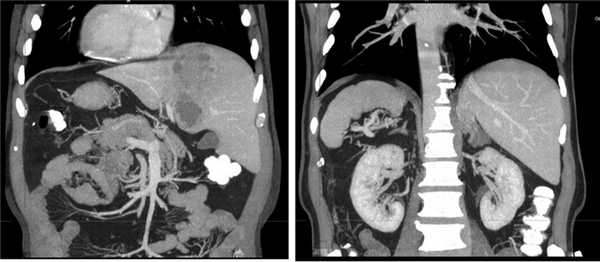

Результаты лабораторных исследований: лейкоциты (WBC) 11,7·10 9 /л; гемоглобин (HGB) 134 г/л, биохимический анализ крови — без отклонений от нормы. Начато проведение антибактериальной терапии (ципрофлоксацин 400 мг 3 раза в день в/в, метронидазол 500 мг 3 раза в день в/в). Учитывая неясный генез образования абсцесса, с целью дообследования была выполнена КТ органов брюшной полости с в/в болюсным усилением, по результатам которого выявлено инородное тело, располагающееся в передней стенке выходного отдела желудка (рис. 1, 2), размерами 30×2 мм с пенетрацией в паренхиму S3 печени и формированием абсцесса 45×35×30 мм (рис. 3, 4).

Рис. 1.ПациентП. КТоргановбрюшнойполостивнативномрежиме. Визуализируются инородное тело и абсцесс печени.

Рис. 2. Пациент П. КТ органов брюшной полости с 3D-реконструкцией. Визуализируется инородное тело.

Рис. 3. Пациент П. КТ органов брюшной полости в венозную фазу, фронтальный срез. Визуализируются инородное тело и абсцесс печени.

Рис. 4. Пациент П. КТ органов брюшной полости в венозную фазу, аксиальный срез. Визуализируется абсцесс печени.